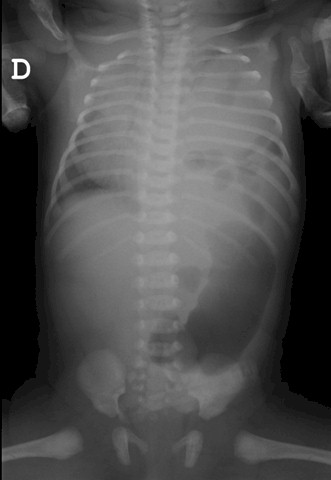

Imágenes radiográficas donde se aprecia consolidación en hemitorax izquierdo e imágenes hidroaéreas con desplazamiento mediastino al lado contralateral